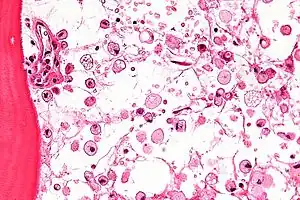

| Micrograph of Gaucher disease, with cells that have the characteristic crumpled tissue paper-like cytoplasm. H&E stain. | |